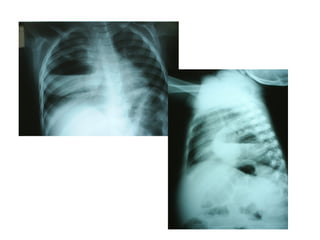

 Derrame pleural

 Pneumatoceles

 Pneumotórax /piopneumotórax

 Pneumonia necrotizante/Abscesso pulmonar

outras.

Complicações

1 2